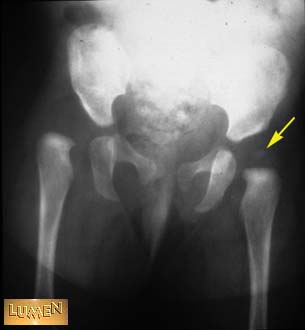

Question: Identify.

Femoral epiphysis.